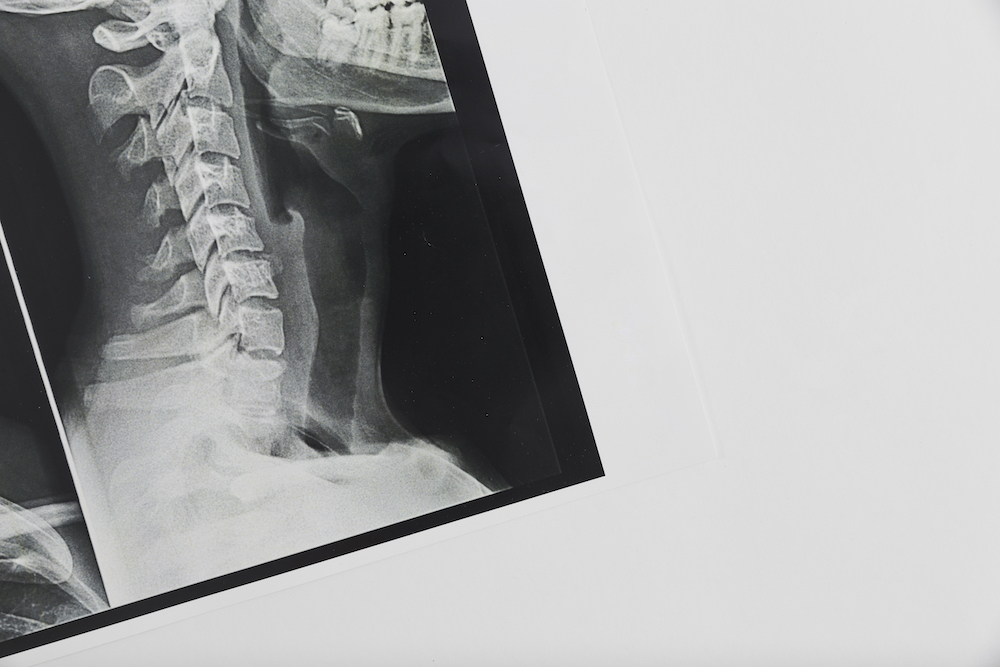

Getting an x-ray of your spine gives us an extremely detailed look at what’s going on with your spine. Many times, this can help us confirm the diagnosis and give us confidence in the right treatment plan to help getting you back to optimal health.

If you’ve been experiencing back pain, neck pain, or headaches, or other discomforts, a spinal x-ray can help us identify the cause and give us a clear path for treatment.

A spinal x-ray can give our chiropractor in Fredericksburg important information about your spine. The imaging can help diagnose problems with your bones, joints, and discs. A spinal x-ray can also help find problems with the ligaments, muscles, and other soft tissues in your back that are tougher to diagnose without the images.

Spine X-rays can reveal herniated discs, scoliosis, degenerative disc disease, arthritis, spinal misalignments, fractures, and other structural problems. At Wilderness Family Chiropractic, Dr. Christine Stewart uses X-rays to guide personalized chiropractic care for patients in Fredericksburg.